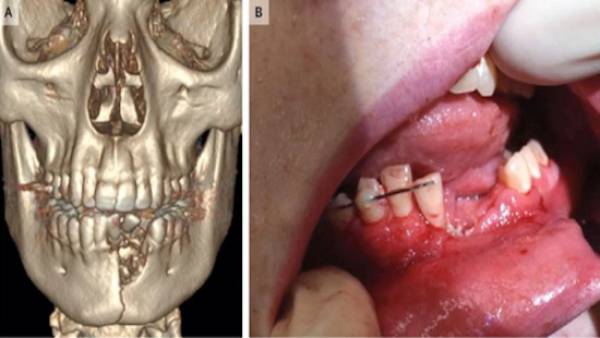

Ảnh chụp xương hàm của bệnh nhân 17 tuổi sau khi thuốc lá điện tử phát nổ

Một thiếu niên có tên Austin Adams, 17 tuổi ở Nevada (Hoa Kỳ) đã đi 250 dặm đến một bệnh viện nhi ở Utah (một tiểu bang miền Tây của Hoa Kỳ) với mẹ của mình do bị th.ươ.ng vì thuốc lá điện t..ử phát nổ. Bệnh nhân nhập viện trong tình trạng có nhiều vết thương ở miệng, nhiều răng bị mất và hàm dưới bị gãy.

Theo bác sĩ Katie Russell - người trực tiếp điều trị cho bệnh nhân, trong quá trình điều trị, họ đã phải nhổ vài chiếc răng ra khỏi miệng vì chân răng bị vỡ, đồng thời đặt một tấm lưới nha khoa ở dưới nướu để ổn định xương hàm.

Sau đó, miệng cậu bé vẫn không khép lại được, cuối cùng, các bác sĩ đã bịt hàm bệnh nhân lại trong 6 tuần để vết thương có thời gian chữa lành.